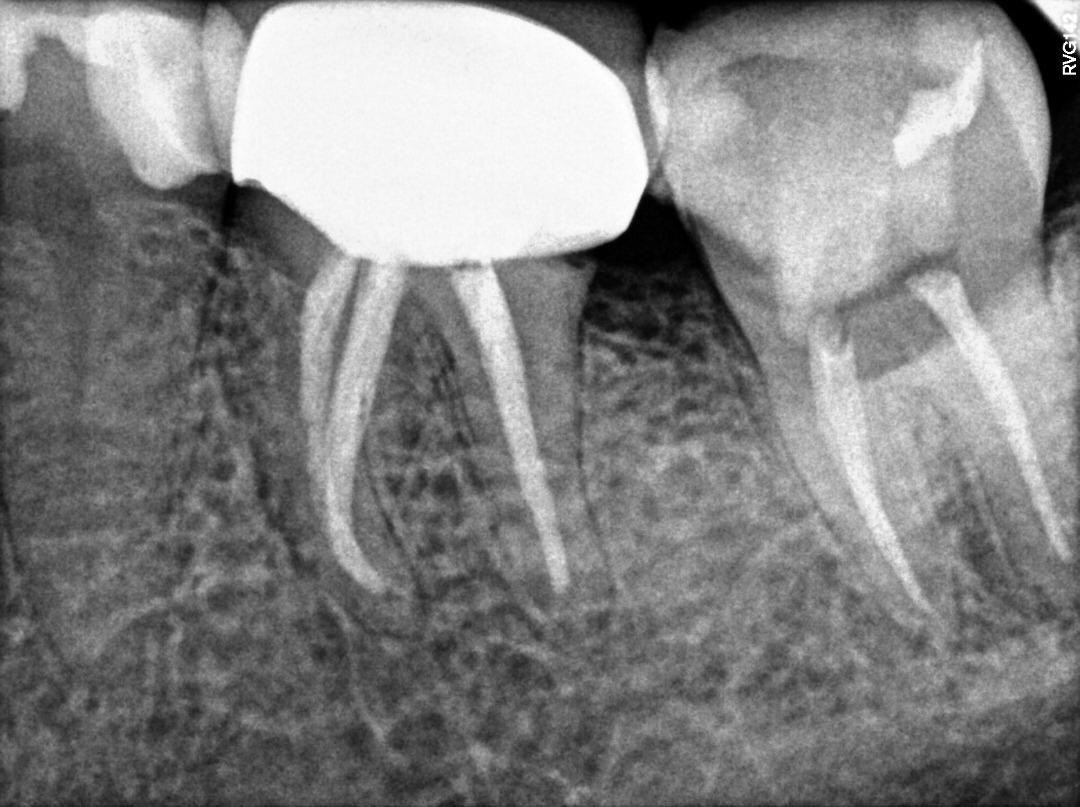

1. Evaluate the root canal treatment of tooth # 2.5?